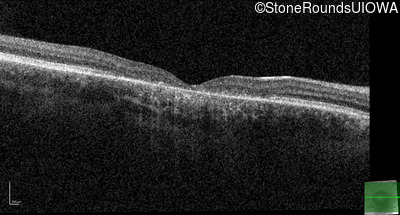

Age at visit: 17 years

OD OS

Age at visit: 17 years (Visit 2)

Age at visit: 21 years

Age at visit: 23 years

Age at visit: 25 years